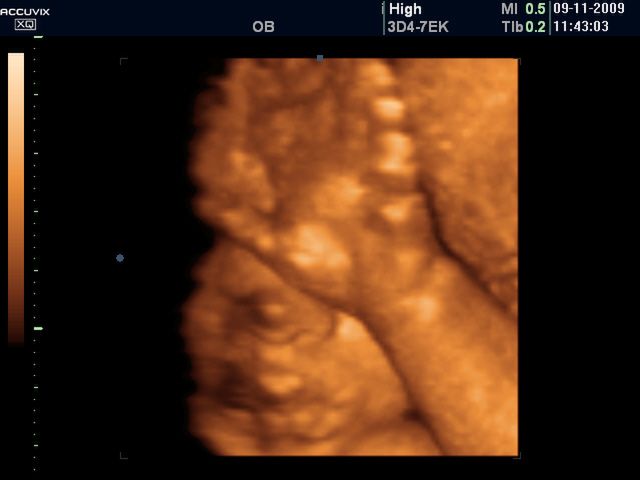

/ 2Płód w 40 tygodniu ciąży - rozmiary dziecka

Płód waży ok. 3,5 kg i mierzy 50 cm wzrostu